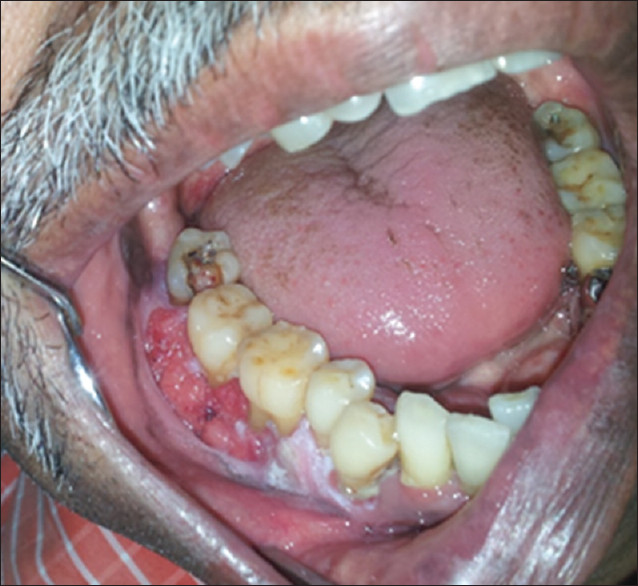

The evidence is overwhelming that smoking contributes to periodontal disease (see Right) and that continued smoking results in a reduced response to periodontal treatment. There is a greater amount of bone loss around teeth in smokers and individuals who smoke are more likely to lose teeth than nonsmokers. It is reported that more than half of advanced gum disease can be linked to tobacco use.

Gingival Recession and Tooth AbrasionIn addition to the development of changes to the oral tissues, the use of smokeless tobacco can damage both the gum tissue and the teeth in the area where it is held in the mouth. Smokeless tobacco can result in localized gum recession and the exposed teeth often develop dental decay due the sweetener in smokeless tobacco. Unfortunately, stopping the tobacco use does not reverse the gum problem or tooth decay.

Oral CancerUse of tobacco products is clearly linked to development of oral cancer (see Below). Oral cancers are found primarily in the floor of the mouth (under the tongue), the sides and underside of the tongue, and the soft palate (the back part of the roof of the mouth). The topic of oral cancer in discussed in a separate Patient Information sheet. The most important key to surviving oral cancer is early detection. The importance of your dentist performing a thorough soft tissue examination cannot be overemphasized. The tissue changes in early cancer can be subtle and it is essential for your dentist to perform a through soft tissue examination to detect cancer at an early stage. He or she may want to take a sample of these tissues (biopsy) for diagnosis, or refer you for this procedure. This is the only way to make a diagnosis of oral cancer, and biopsy can also help in determining your long-term outlook.